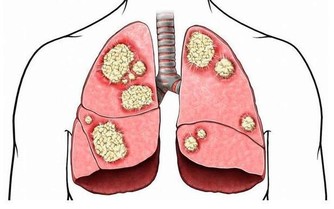

銀耳燴,能清肺。

吃百合,益補肺。